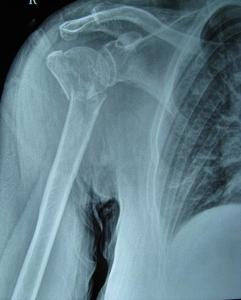

♥肱骨外髁颈骨折

肱骨外髁颈位于解剖颈下方2~3cm,是肱骨头松质骨和肱骨干皮质骨交界的部位,很易发生骨折。各种年龄均可发生,老年人较多。